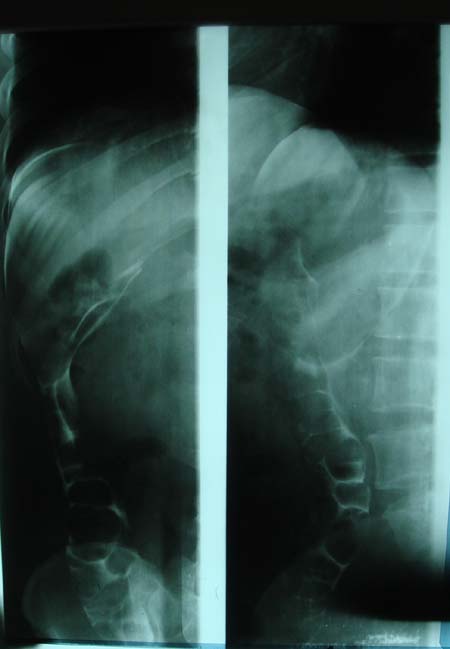

以下是引用dyqct在2009-8-23 16:17:00的发言:[br]考虑:1、造影剂进入腹腔、结肠旁沟、肝周;[br] 2、子宫明显增大(腺肌增生症?);[br] 3、膀胱显影是由于造影剂吸收后经肾分泌进入膀胱的;[br] 4、建议mri检查子宫。